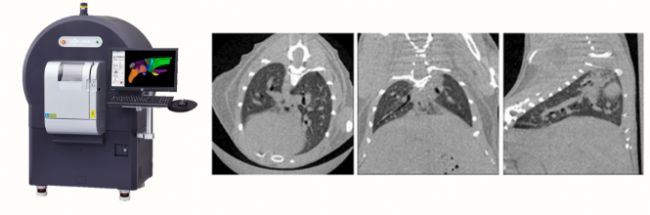

利用軟件進(jìn)行閾值分割后,可以將左肺和右肺的參數(shù)分別進(jìn)行統(tǒng)計(jì)。如下圖是一只健康小鼠肺部斷層和3D重建后的體渲染圖,左側(cè)顯示了典型的兩個(gè)呼吸時(shí)間點(diǎn)——吸氣末期和呼氣末期肺的狀態(tài)。能夠看到兩個(gè)時(shí)間點(diǎn)之間,由于空氣含量不同,肺的體積和平均密度均有顯著的差異。通過這兩個(gè)時(shí)間點(diǎn),即可得到功能余氣量(FRC)和潮氣量(VT)。再通過每一個(gè)時(shí)間點(diǎn)的容積和相鄰時(shí)間點(diǎn)之間的容積差ΔV,即可得到容積(V)-時(shí)間(t)、流量(ΔV)-時(shí)間(t)和流量-容積環(huán)圖等功能性曲線。可以看到,健康小鼠的雙肺功能健全,不論是肺容積和流量變化均顯示出完美的一致性。

圖二 健康小鼠肺容積與流量示意圖 (左:呼氣末期和吸氣末期的冠狀面斷層與3D體渲染圖;中:容積(V)-時(shí)間(t)、流量(ΔV)-時(shí)間(t)曲線;右:流量-容積環(huán)圖;黑色實(shí)線:全肺參數(shù);藍(lán)色虛線:右肺數(shù)據(jù);綠色虛線:左肺數(shù)據(jù))